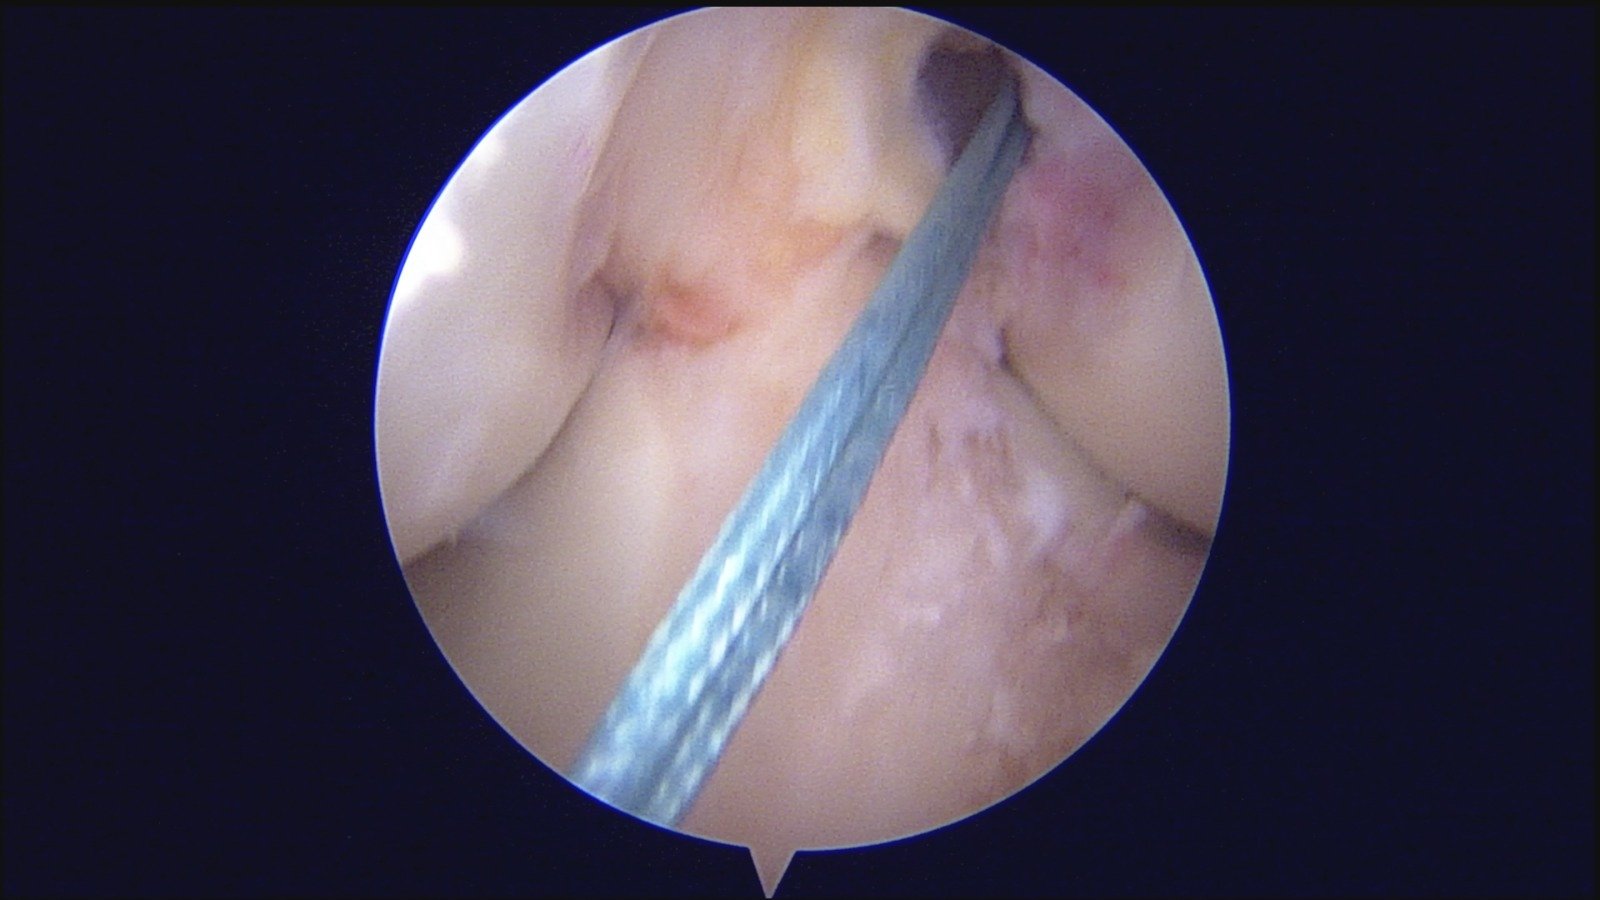

GalleryShoulder rotator cuff repair Meniscus root repair Meniscus repair Bankart repair for recurrent shoulder dislocation ACL reconstruction Machines Instruments